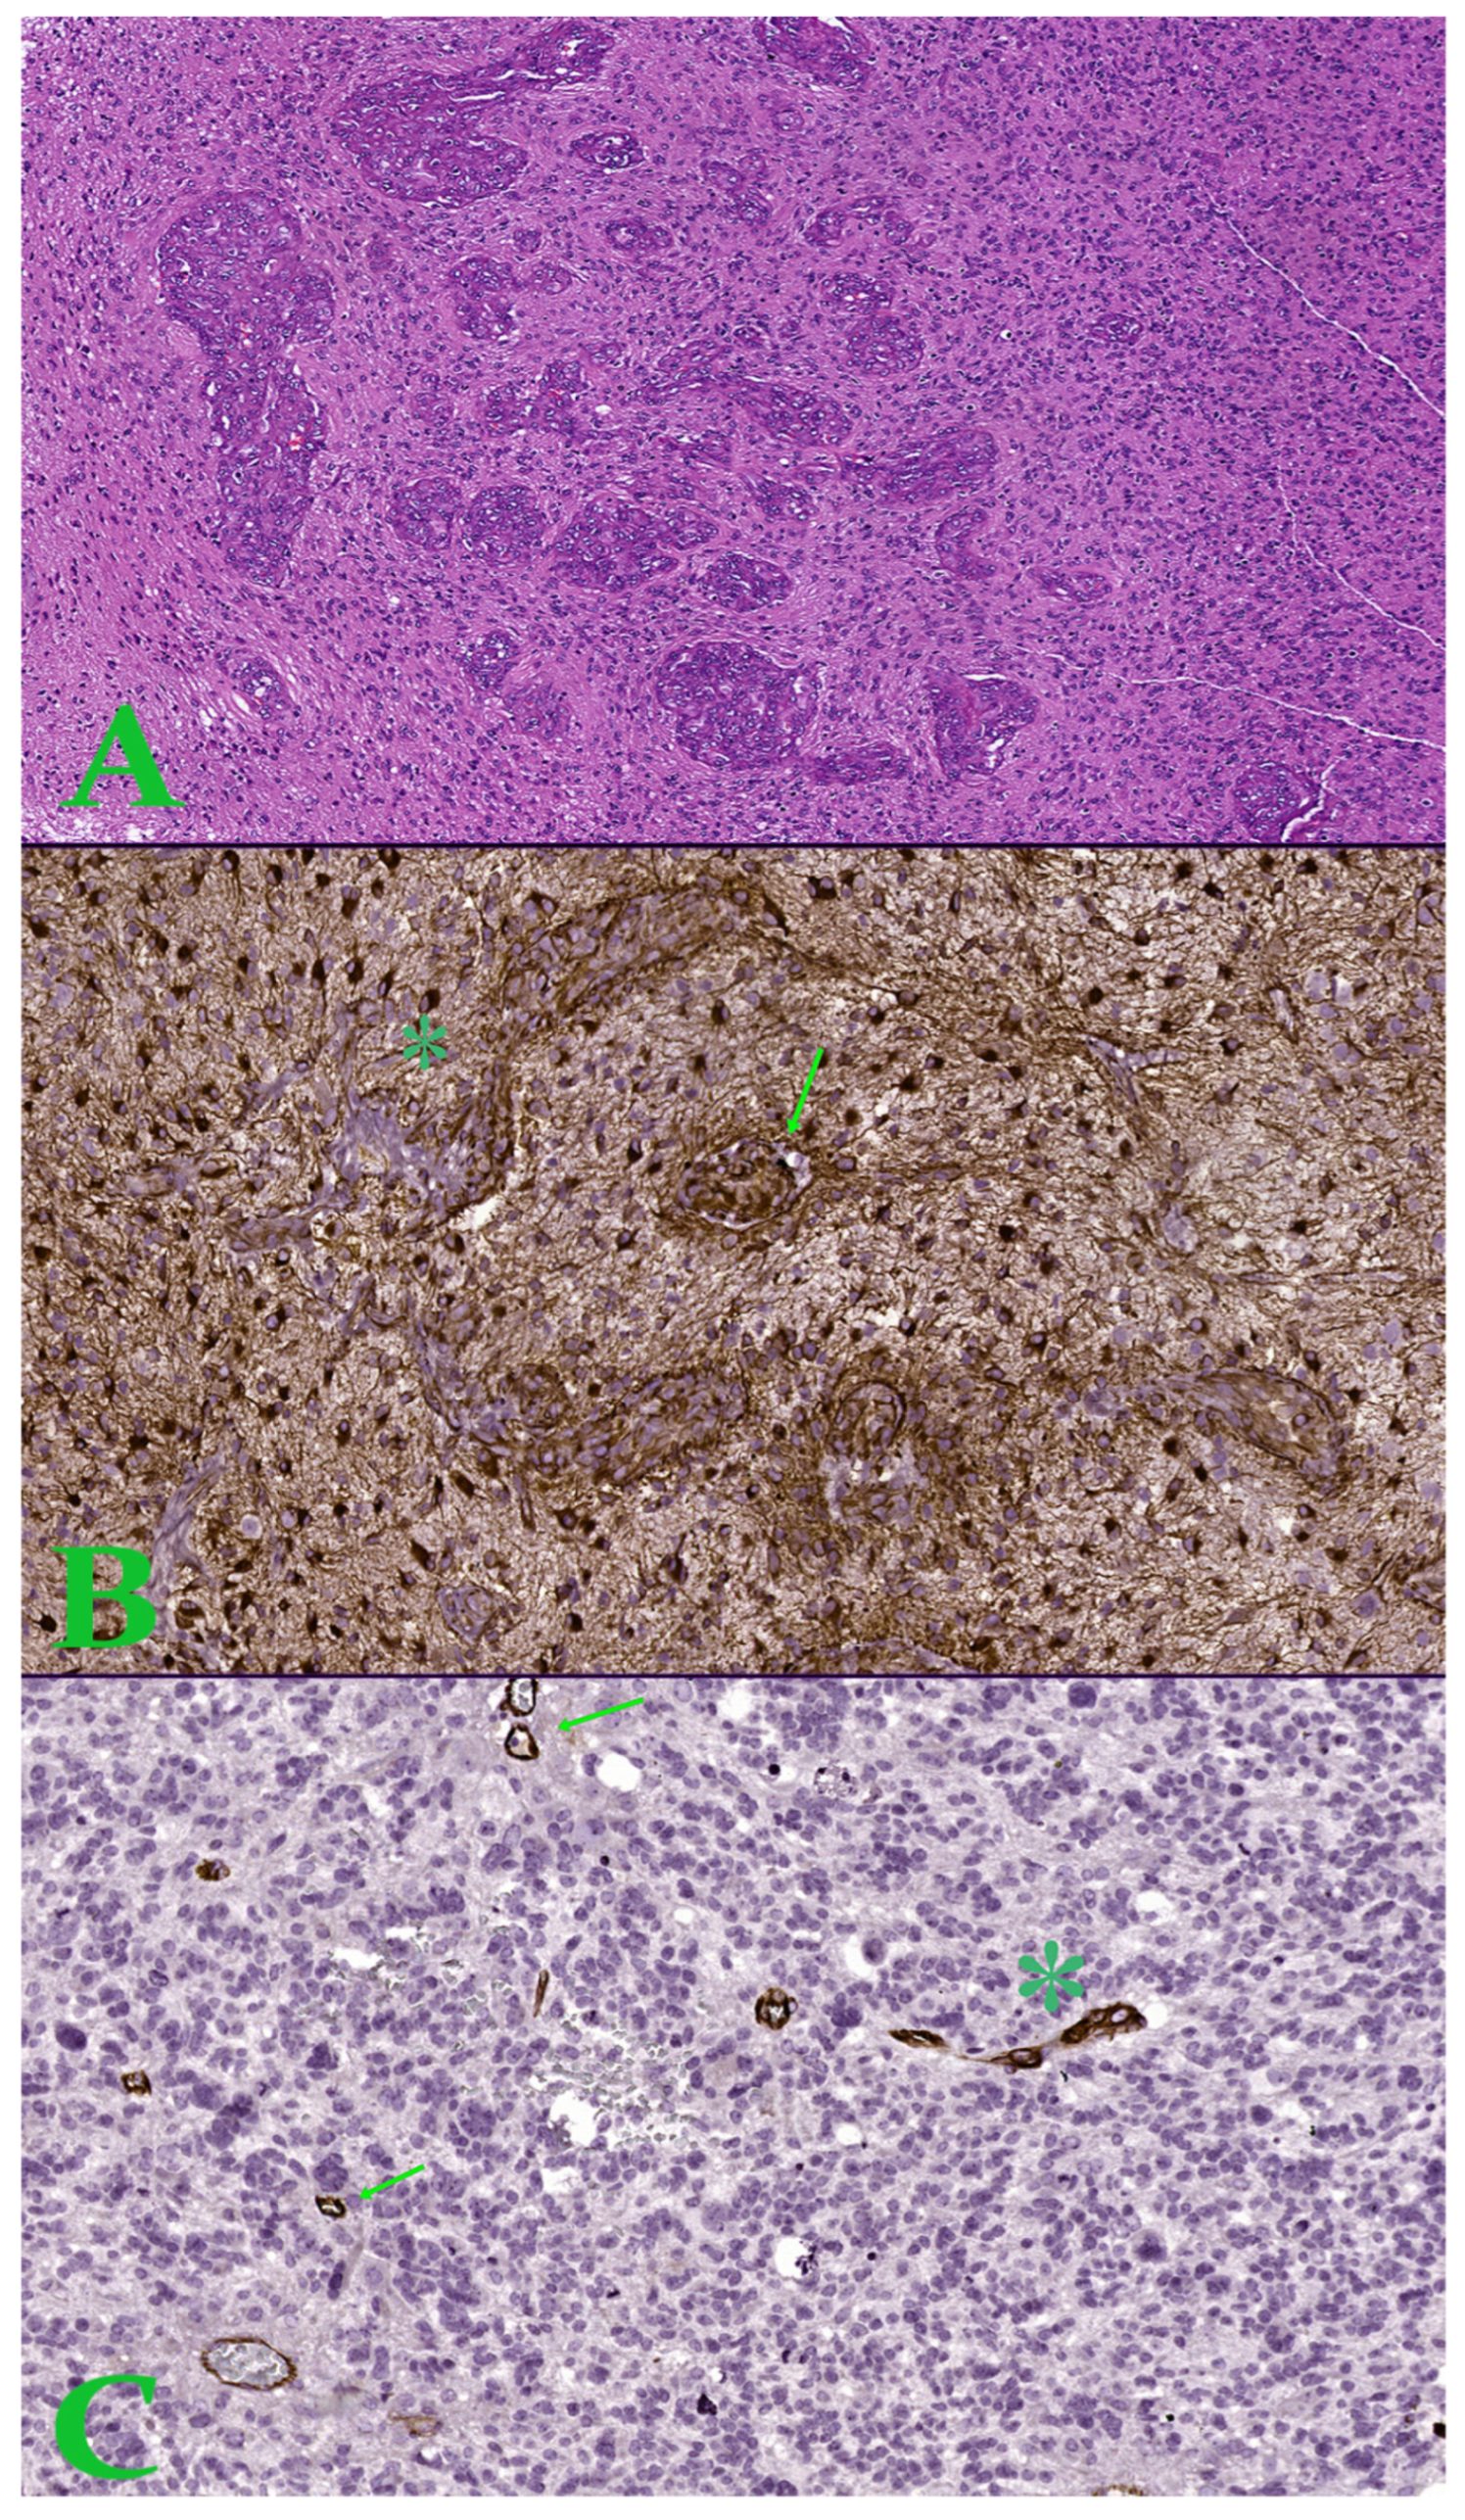

Figure 3. (A). Image in hematoxylin-eosin, which shows an area of microvascular proliferation. Ob. x50. (B). Hot-spot of 1 mm2 with increased microvascular density showing proliferation of glomeruloid tuft type (arrow) and vascular garland (asterisk)—Nestin stain. (C). Hot-spot of 1 mm2 with increased microvascular density showing microvascular sprouting (arrow) and microvascular clustering (asterisk)—Nestin stain.

Six immunohistochemical markers were performed within CEDMOG. Immunohistochemical assays were performed by the HIER-DAB method and employed the following markers: IDH1 R132H (clone H09), Ki-67 (clone SP6), PTEN (phosphatase and tensin homolog, clone 6H2.1), p53 (clone SP5), Nestin (clone 10C2), and MGMT (clone MT 23.2) (Figure 2). The stratification of cases was due to the IDH1 R132H immunomarker. The Ki-67 index was determined by calculating the percentage of positive nuclei, based on the assessment of a minimum of 10 high-power fields, totaling at least 1000 nuclei. The PTEN was assessed at both the cytoplasmic and nuclear levels. An expression above 10% was considered positive for p53 [13,14]. The assessment of Nestin involved evaluating the cytoplasmic immunoreactivity of glial cells across three levels (weak, moderate, or strong) and determining the reactivity (negative or positive) in endothelial cells (Figure 3). Slides were converted to digital format using a TissueScope LE120 Slide Scanner (Huron Digital Pathology, Ontario, CA, USA). Following that, were identified ten microvascular hotspot regions, each measuring 1 mm2. The average count of capillary vessels assessed by two pathologists was divided by ten to yield the mean number of vessels per 1 mm2. To quantify necrosis, the tumor section was divided into 100 squares. Where necrosis was present, the square was shaded. The sum of the shaded squares represents the necrotic percentage (Figure 4). The nuclear level of MGMT was evaluated in glial tumor cells, and the results were subsequently categorized as >50%, 10–50%, and <10%.

Angiogenesis is an essential factor in tumor growth. Proangiogenic factors, such as Vascular Endothelial Growth Factor (VEGF), are a consequence of hypoxia, stimulating microvascular proliferation and neoangiogenesis. VEGF is a pro-angiogenic factor by stimulating endothelial cell proliferation, migration, and mitotic stimulation of these cells, resulting in the proliferation of new vessels with a role in tumor progression [4,8]. Four patterns of vascular proliferation have been identified, such as microvascular sprouting, microvascular clustering, vascular garland, and glomeruloid tuft. Microvascular sprouting is characterized by the presence of small capillary-like vessels, distributed diffusely and uniformly throughout the vital tumor tissue. Microvascular clustering is characterized by small vessels arranged in groups (minimum 3 vessels) without the presence of stroma between them [9,10]. A vascular garland is a group of small vessels arranged in a garland-like manner. Intervening conjunctival stroma may or may not be present. This vascular pattern is particularly common around necrotic tissue. A glomeruloid tuft is a group of vessels with intervening stroma, in which pericytes and endothelial cells form dysfunctional, poorly organized structures with an architecture similar to renal glomeruli [9,10,11].